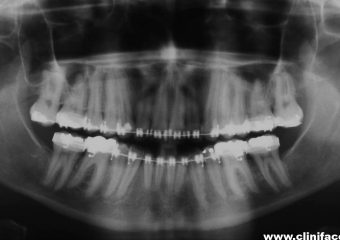

Raio x panorâmico final